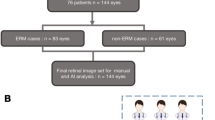

In this study, the exclusion criteria were as follows: keratoconus, high myopia (more severe than -6 diopters or ocular axial length > 26.5 mm), prior intraocular surgery or any co-existing ocular disease. Under this criterion, 72 image sets (color fundus image, 570-nm image, and the 610-nm image) were obtained from 51 Chinese ethnic subjects. Among them, 23 people were patients diagnosed with iERM by two physicians with clinical experience from Wenzhou Medical University, and 28 were healthy control subjects. The average age of the iERM group was \(59.7\pm 6.0\), with 8 males and 15 females. The average age of the control group was \(57.6\pm 6.1\), with 9 males and 19 females. There was no significant difference in age between iERM and the normal control group, and neither had other systemic diseases. The demographic data of iERM and the normal control group are shown in Table1.